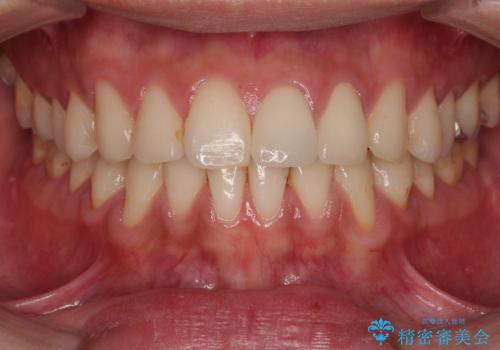

前歯の根のところに違和感がある|根尖性歯周炎|精密根管治療|オールセラミッククラウン|見た目も改善